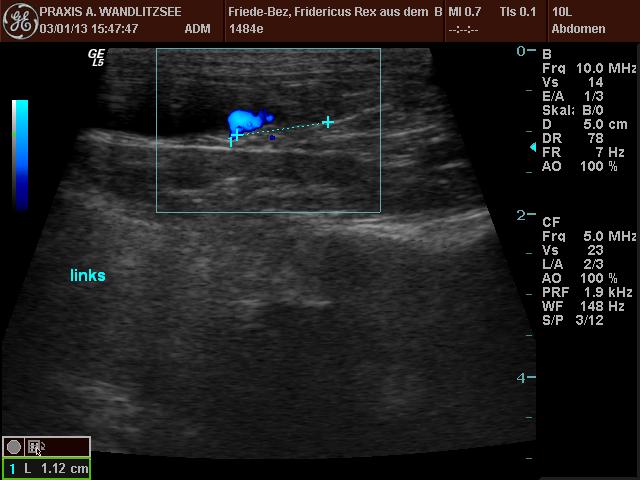

Die Ultraschalluntersuchung hat ein wenig länger gedauert als erwartet, da das harntreibende Mittel offenbar einige Zeit brauchte, seine Wirkung zu entfalten. Dann waren aber schöne "Jets" zu sehen, und zwar da, wo sie sein sollten. Grund zur Freude also. Welpi wurde die Zeit lang und er schlief ein, während der Doktor ihm mit dem Sonar über den Bauch fuhr.

20130103 Fridericus Rex eU Ultraschall links